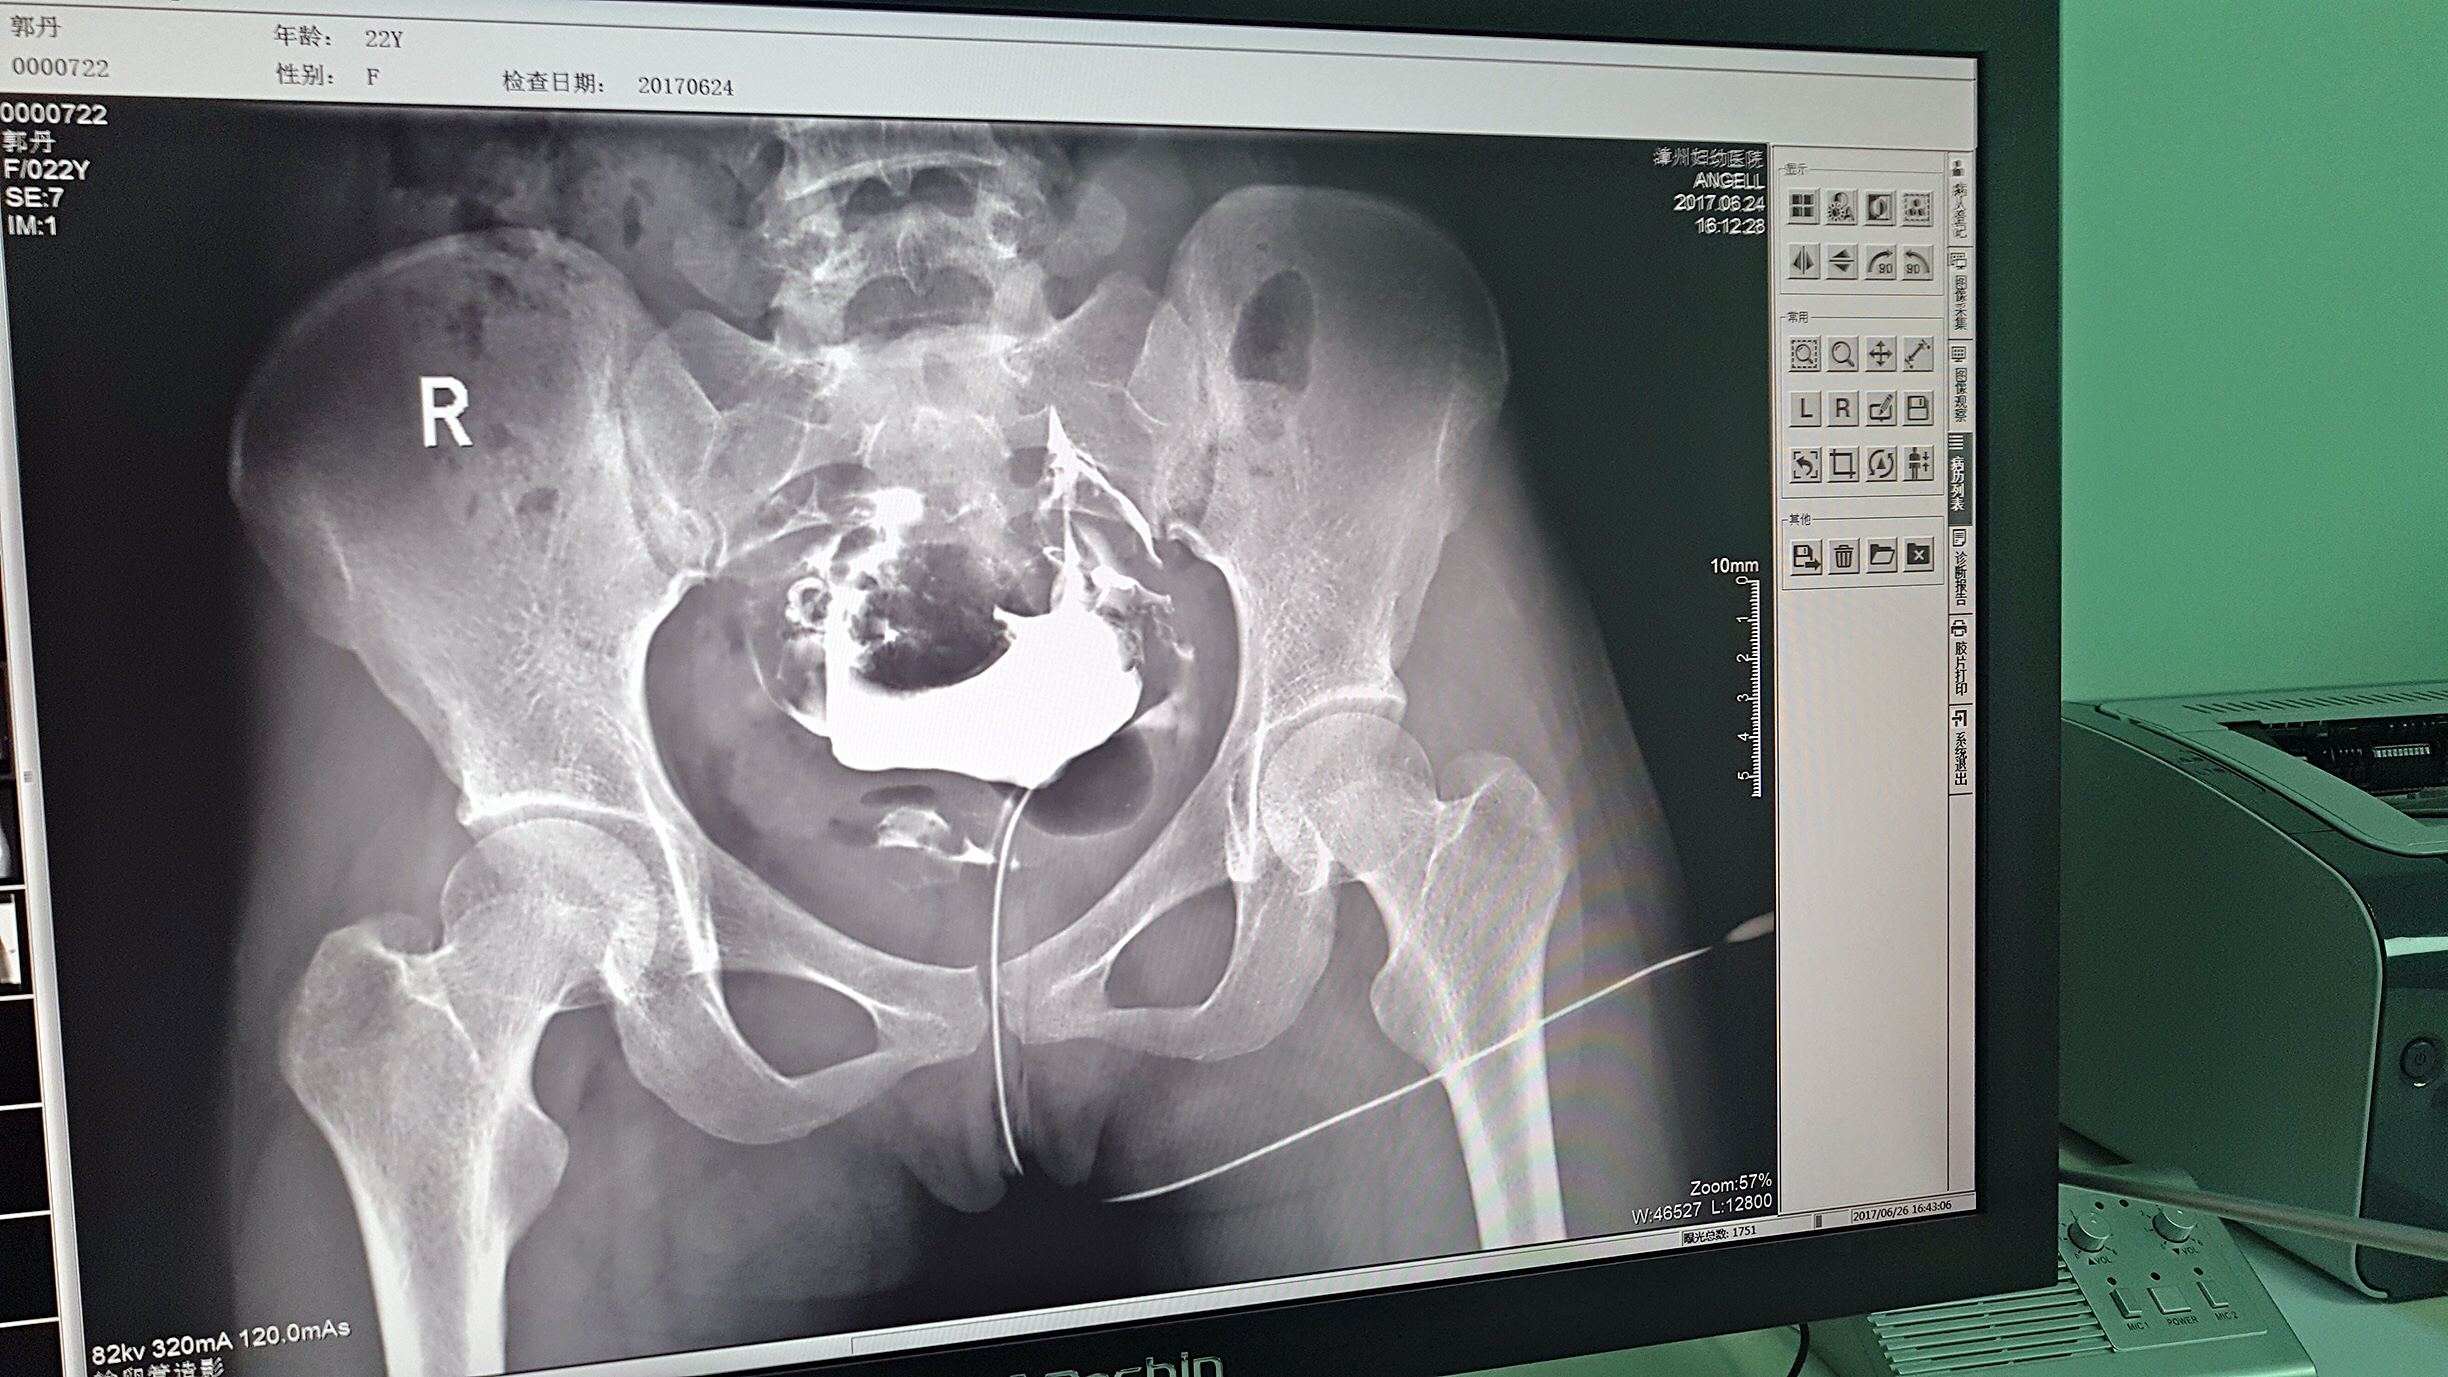

目前設(shè)備除了用于常規(guī)拍片之外,主要用于輸卵管造影檢查,平均每個(gè)月有超過20個(gè)患者在漳州婦幼醫(yī)院做輸卵管造影檢查。在此之前,漳州市只有市醫(yī)院、175解放軍區(qū)醫(yī)院等大三甲醫(yī)院才能做輸卵管造影檢查,這不僅讓三甲醫(yī)院人滿為患,而且下級(jí)醫(yī)院卻因?yàn)椴荒茏瞿稠?xiàng)檢查而造成資源浪費(fèi)。因?yàn)橛辛嗽O(shè)備,漳州婦幼醫(yī)院可以滿足患者的一些特殊檢查需求,已經(jīng)有很多患者慕名而來(lái)。

漳州婦幼醫(yī)院放射科的陳主任日常跟這臺(tái)設(shè)備打交道是最多的,他最有發(fā)言權(quán)。在安健科技的回訪中,陳主任說:這臺(tái)設(shè)備具備先進(jìn)的診斷功能,操作方便,能夠拍攝出清晰的影片,進(jìn)而對(duì)患者病情能夠?qū)崿F(xiàn)精準(zhǔn)診斷。同時(shí)在醫(yī)院對(duì)患者診斷能力方面有較大提升,留住了大量患者,為患者提供了更好的醫(yī)療服務(wù)。